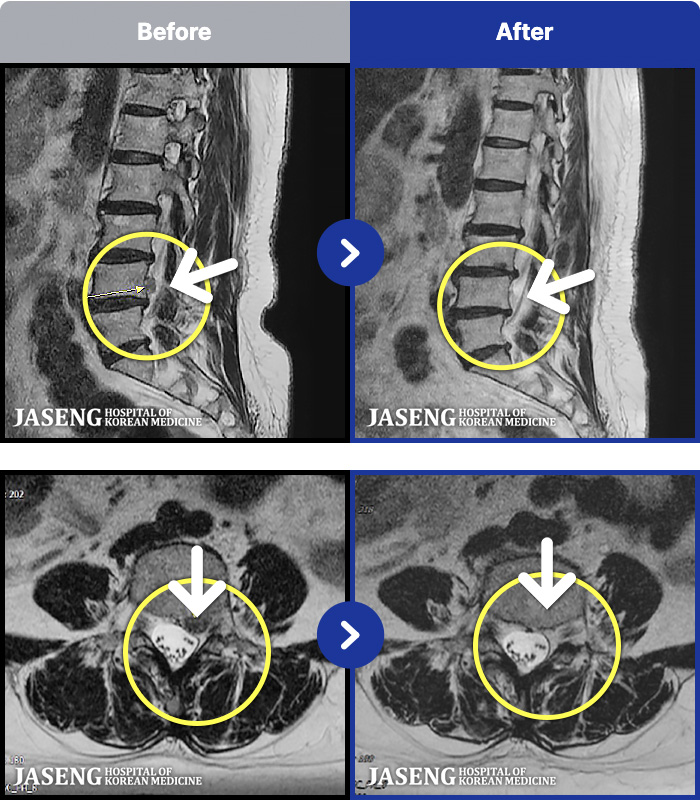

MRI ġ

MRI ũ ʸ Ȯϼ.